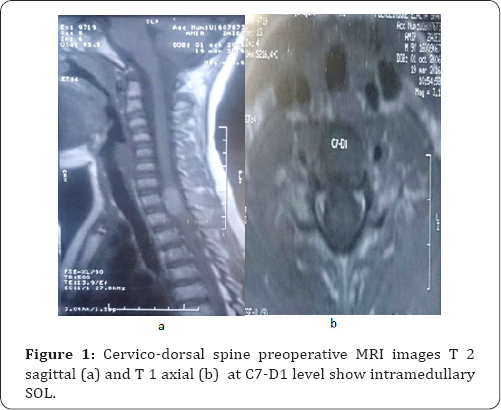

Radiological findings

The radiologist was diagnosed the lesion as intramedullary S.O.L as the imaging study demonstrated a swollen spinal cord with the intramedullary well circumscribed cystic lesion extending from C7 til D2, no dermal sinus tract and the dimple can also be noticed on the MRI and we decided the surgery for biopsy (Figure 1).